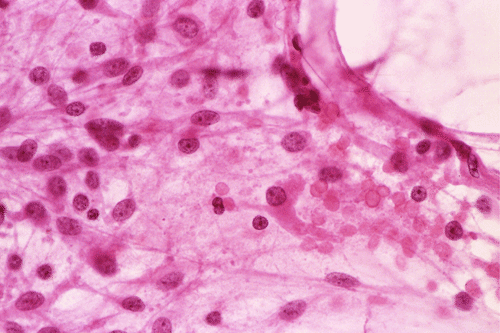

Microscopically, pilocytic astrocytomas characteristically contain alternating densely packed areas and loosely packed areas. The cellularity is moderate but can be focally hypocellular or hypercellular. The tumor cells have elongated, coarse, hair-like cytoplasmic processes. The nuclei are usually bland, small to medium sized and has open chromatin. A variety of patterns can be seen. The loose tissue is composed of minute vacuoles, microcysts, and eosinophilic fluid-filled spaces, which can coalesce into larger structures. A variety of histologic patterns as illustrated in this case can be found. Rosenthal fibers, varying in amount from a few to substantial, may be found and are particularly common in the fibrillary areas. Eosinophilic granular bodies are aggregates of eosinophilic globules and they are often found in pilocytic astrocytoma. Their presence is related to the benign nature of these tumors. Glomeruloids of blood thin walled blood vessels are also common findings. Extension into the leptomeninges is common and does not signify malignant behavior. Tumor necrosis is an uncommon features and should be distinguished from infarction of tumor. In longstanding cases, degenerative atypia may occur. The proportion of cycling cells as measured by immunohistochemistry for Ki67 is usually under 5%. Occasional mitoses may be found but they are not indication of aggressive behavior.

Comment: This case illustrated the diversified histologic features that can be seen in some pilocytic astrocytomas.

DIAGNOSIS: Pilocytic astrocytoma. (WHO grade I/IV)